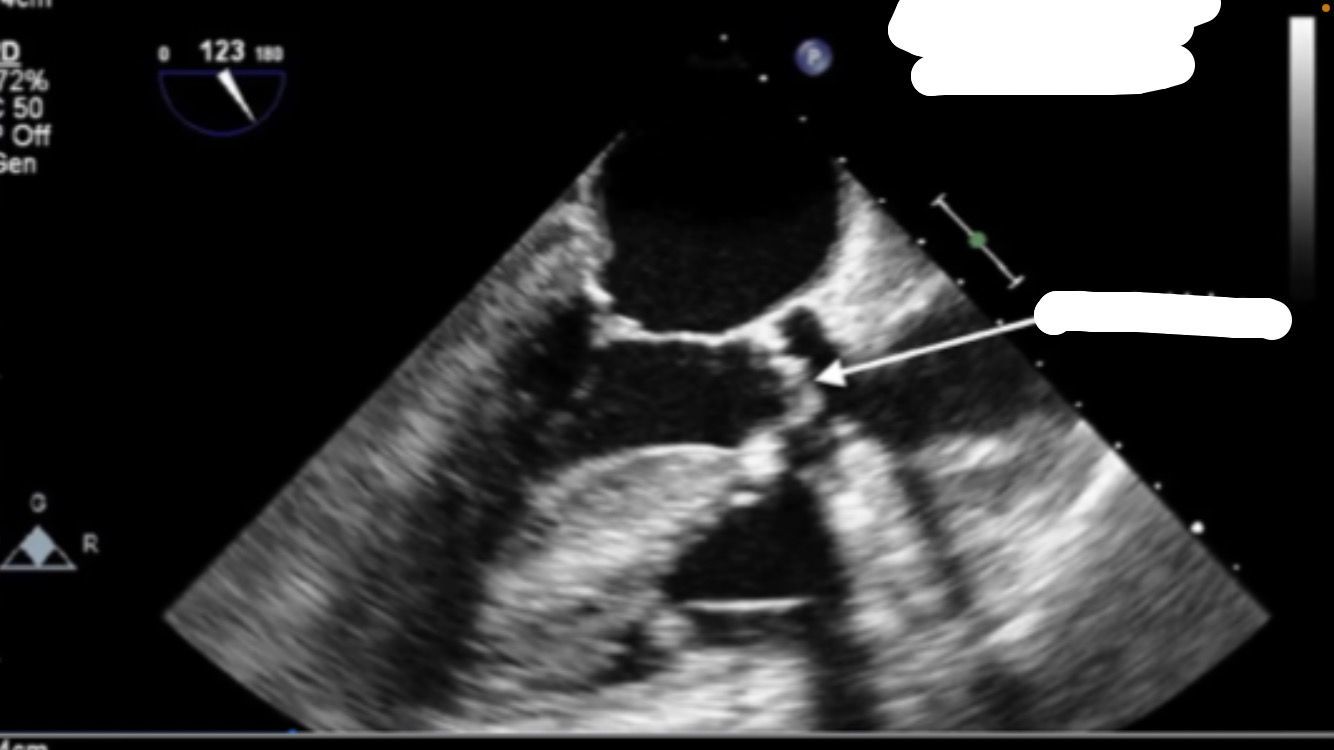

Bicaval view

PFO